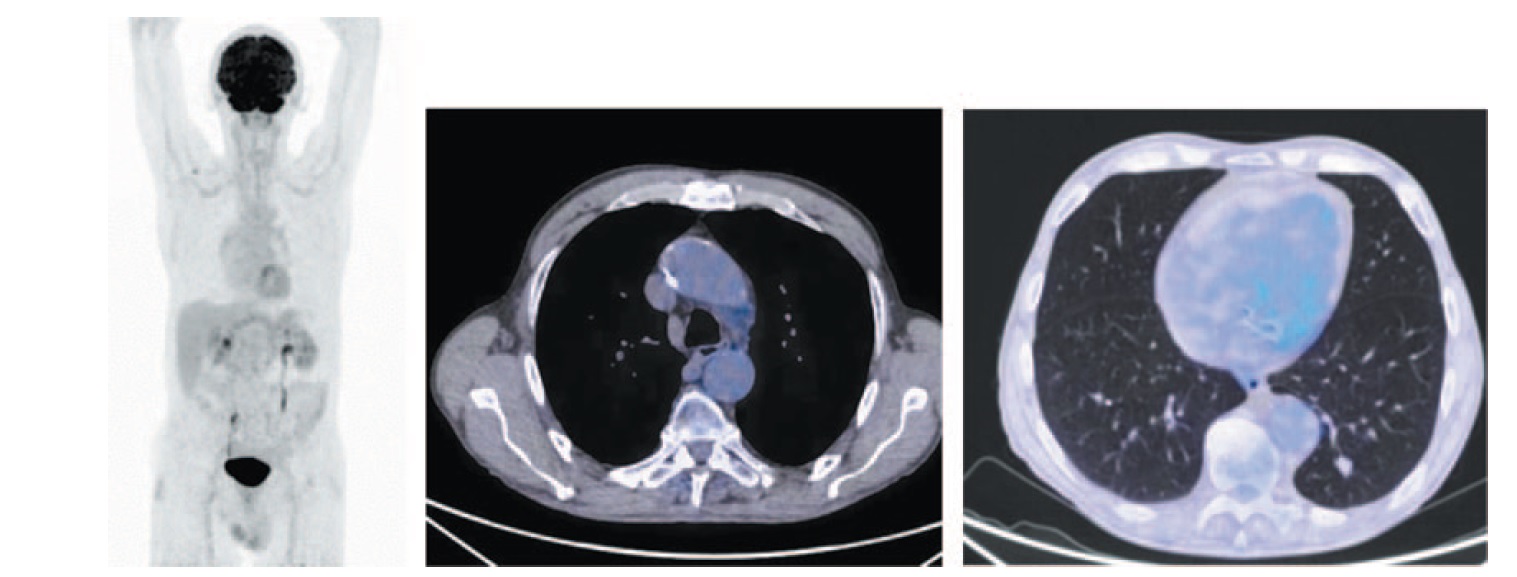

После 10-го введения атезолизумаба (через 7 мес от начала лечения) произведено ПЭТ/КТ-исследование. Объем нижней доли левого легкого восстановлен. На месте патологического образования отмечается фиброзный тяж без метаболической активности ФДГ. Надключичный лимфатический узел справа не определяется. В плевральных полостях и полости перикарда экссудата нет. Лимфоузлы средостения не выявлены (рис. 3). Отмечается полная регрессия опухоли по критериям RECIST v.1.1. и полный морфо-метаболический ответ по результатам ПЭТ/КТ.

Рис. 3. Больной П., 76 лет, после 10 введений атезолизумаба (через 6 мес от начала лечения). На МIP- и аксиальных ПЭТ/КТ-проекциях надключичный лимфоузел справа не визуализируется. В нижней доле левого легкого на месте патологического образования определяется тяж фиброза с узловым образованием (желтая стрелка) в структуре размером до 13×14 мм (ранее 15×16 мм) без метаболической активности ФДГ. Отмечается регресс цепочки паратрахеальных лимфоузлов с верхнего уровня до бифуркации. Лимфоузлы аортопульмонального окна размером до 10×12 мм (красная стрелка). / Fig. 3. A 76-year-old patient P. after 10 injections of atezolizumab (6 months after the start of treatment). MIP and axial PET/CT images did not show the right supraclavicular lymph. In the lower lobe of the left lung at the site of the pathological lesion, a band of fibrous tissue with a nodular formation (yellow arrow) is determined in a structure measuring 13×14 mm (previously 15×16 mm) without FDG metabolic activity. There is a regression of the paratracheal lymph nodes from the upper level to the bifurcation. Aortopulmonary window lymph nodes are measuring 10×12 mm (red arrow).